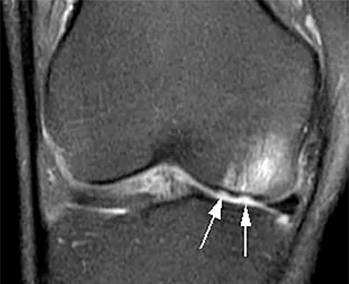

6 | Existe algum exame de imagem que confirme a lesão?

Sim. A Ressonância Magnética, por exemplo, é um exame extremamente útil. Os aparelhos mais modernos mostram a lesão com detalhes, inclusive com estudo do seu metabolismo.